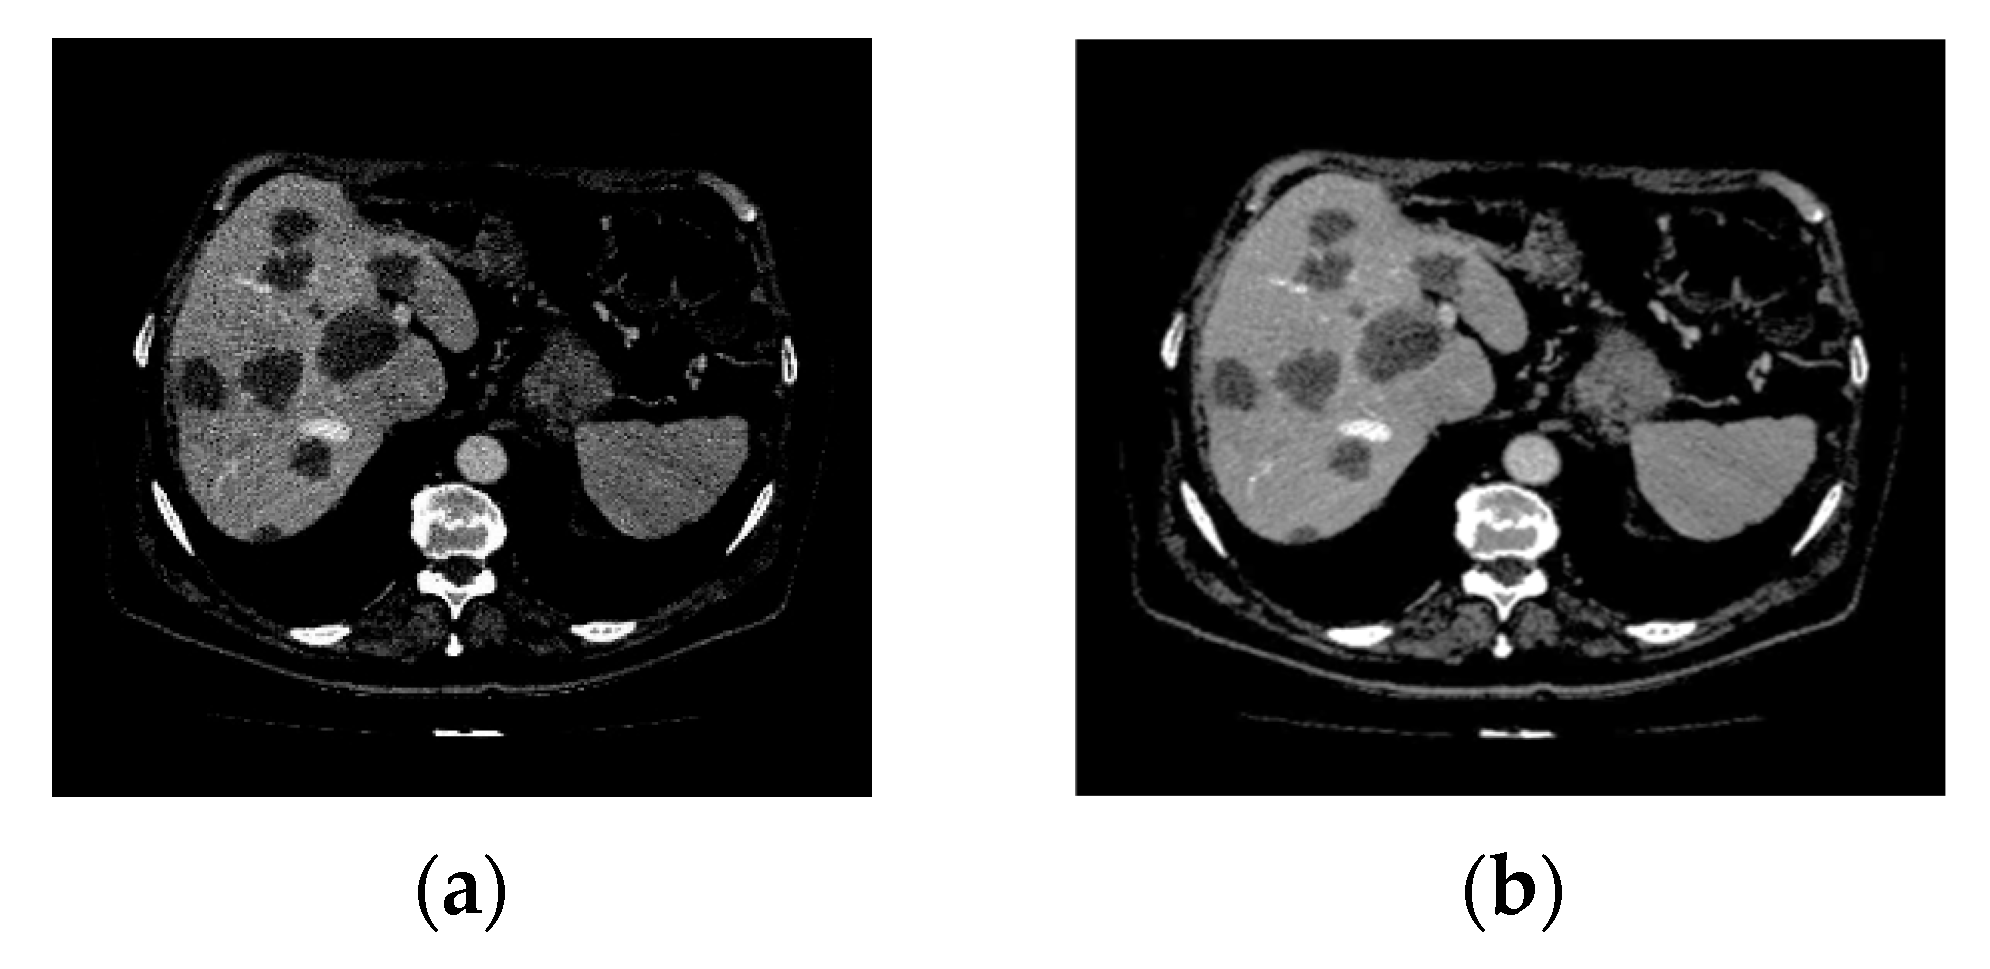

The pre-processing stage is crucial for improving image quality during network training. This stage involves several steps designed to enhance image quality and feature extraction for the segmentation task. First, windowing is applied within a specified Hounsfield Unit (HU) range of −200 to 200. This technique eliminates irrelevant tissues by focusing on the HU values typically associated with liver tissue. Furthermore, voxel values are normalized by scaling them from −1 to 1, enhancing the network’s training. Moreover, data augmentation techniques, including random flips and rotations, enhance the dataset size. The raw image provides intricate spatial information, whereas the SWT-processed image presents a multi-resolution viewpoint, as illustrated in Figure 1.

4.3.1. Pre-Processing Evaluation

Figure 8 shows the original and pre-processed images. The experimental results demonstrate the effectiveness of the image enhancement methodology, as presented in Table 1. The metrics used for evaluation are the Structural Similarity Index (SSIM) [44] and Peak Signal-to-Noise Ratio (PSNR) [45], which are widely regarded as reliable indicators of image quality in enhancement tasks. Higher values of both the SSIM and PSNR indicate the better preservation of structural information and improved image clarity after pre-processing.

Figure 8. 3DIRCADb dataset. (a) Original CT scan; (b) pre-processed image.